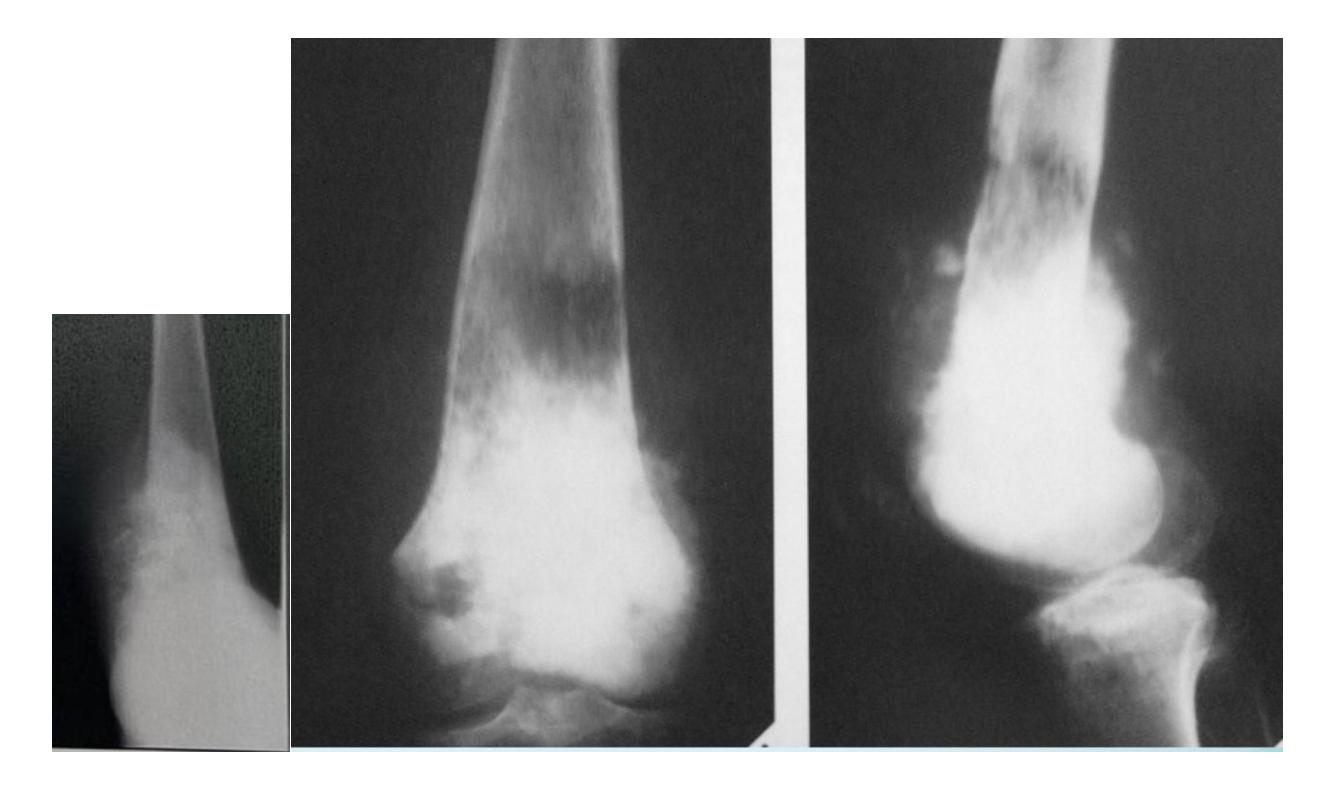

Clinical Cases:

-

14-year-old patient with pain and swelling at lower right thigh

- Most important X-ray findings: Sun ray appearance, Codmanโs triangle

- Diagnosis: Osteosarcoma

14-year-old patient complaining of pain and swelling at lower R thigh

- Findings: Codmanโs triangle, Sun burst appearance

Codman trinagle